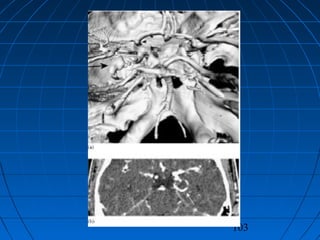

MASİF SPONTAN SAK + ICH + İVH + SDH…MASİF SPONTAN SAK + ICH + İVH + SDH…

MASİF SPONTAN SAK + ICH + İVH +…MASİF SPONTAN SAK + ICH + İVH +…

• 58 yaşında bayan hasta58 yaşında bayan hasta

• Ani bilinç kaybı şikayetiyle acilAni bilinç kaybı şikayetiyle acil

polikliniğe getirildipolikliniğe getirildi

• İlk NM:İlk NM: Bilinç kapalı; GKS: 5Bilinç kapalı; GKS: 5

Pupillalar anizokorikPupillalar anizokorik

YBÜYBÜ

5. günde exitus5. günde exitus